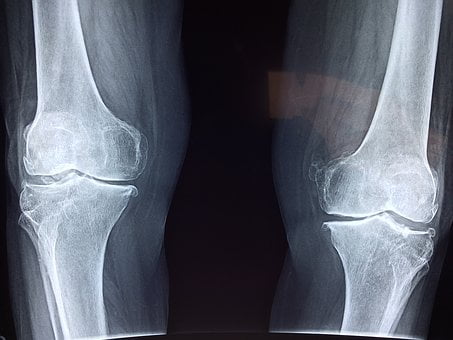

Tre medicinali che possono danneggiare le ossa e aumentare il rischio di fratture

Tre medicinali che possono danneggiare le ossa. Tutti sappiamo che qualunque farmaco può avere degli effetti collaterali. Del resto, non è per caso che in greco antico pharmakon significava sia farmaco che veleno.   In questo articolo ci chiediamo, in particolare, se l’uso prolungato di certi farmaci possa danneggiare le ossa. Di questi medicinali potenzialmente … Leggi tutto